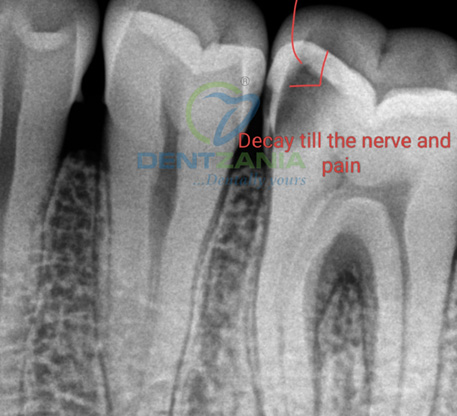

A toothache often needs some sort of treatment by your dentist. The treatment will depend on the underlying cause . However , for a disturbing pain originating from the tooth due to decay or excessive loss of enamel , a root canal treatment provides immediate relief and is the preferred treatment option when the tooth is salvageable !

A root canal is a dental procedure that saves a damaged or infected tooth by replacing the tooth's pulp with a filling and is the most common treatment for a tooth ache that is severe and caused by nerve irritation . It's also known as endodontic treatment. Rootcanals almost instantly relieve a long standing or severe toothache that is caused due to nerve irritation or infection . There is a mystique surrounding Root Canal Treatments, and the reality is that they are not half as bad as people think.

- Decay has reached the tooth pulp (the living tissue inside the tooth).

- Severe toothache.